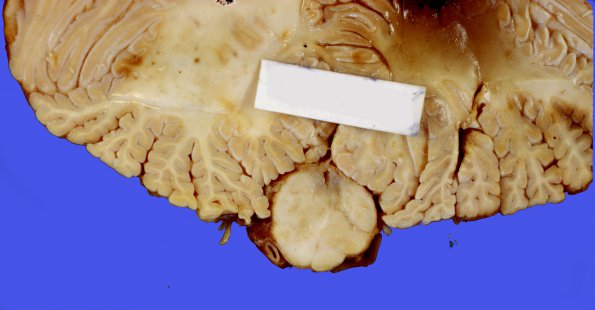

This 12 year old leukemic patient spontaneously developed syrinxes in both the medulla (syringobulbia, image #1A1) and spinal cord (images #1A2,3).